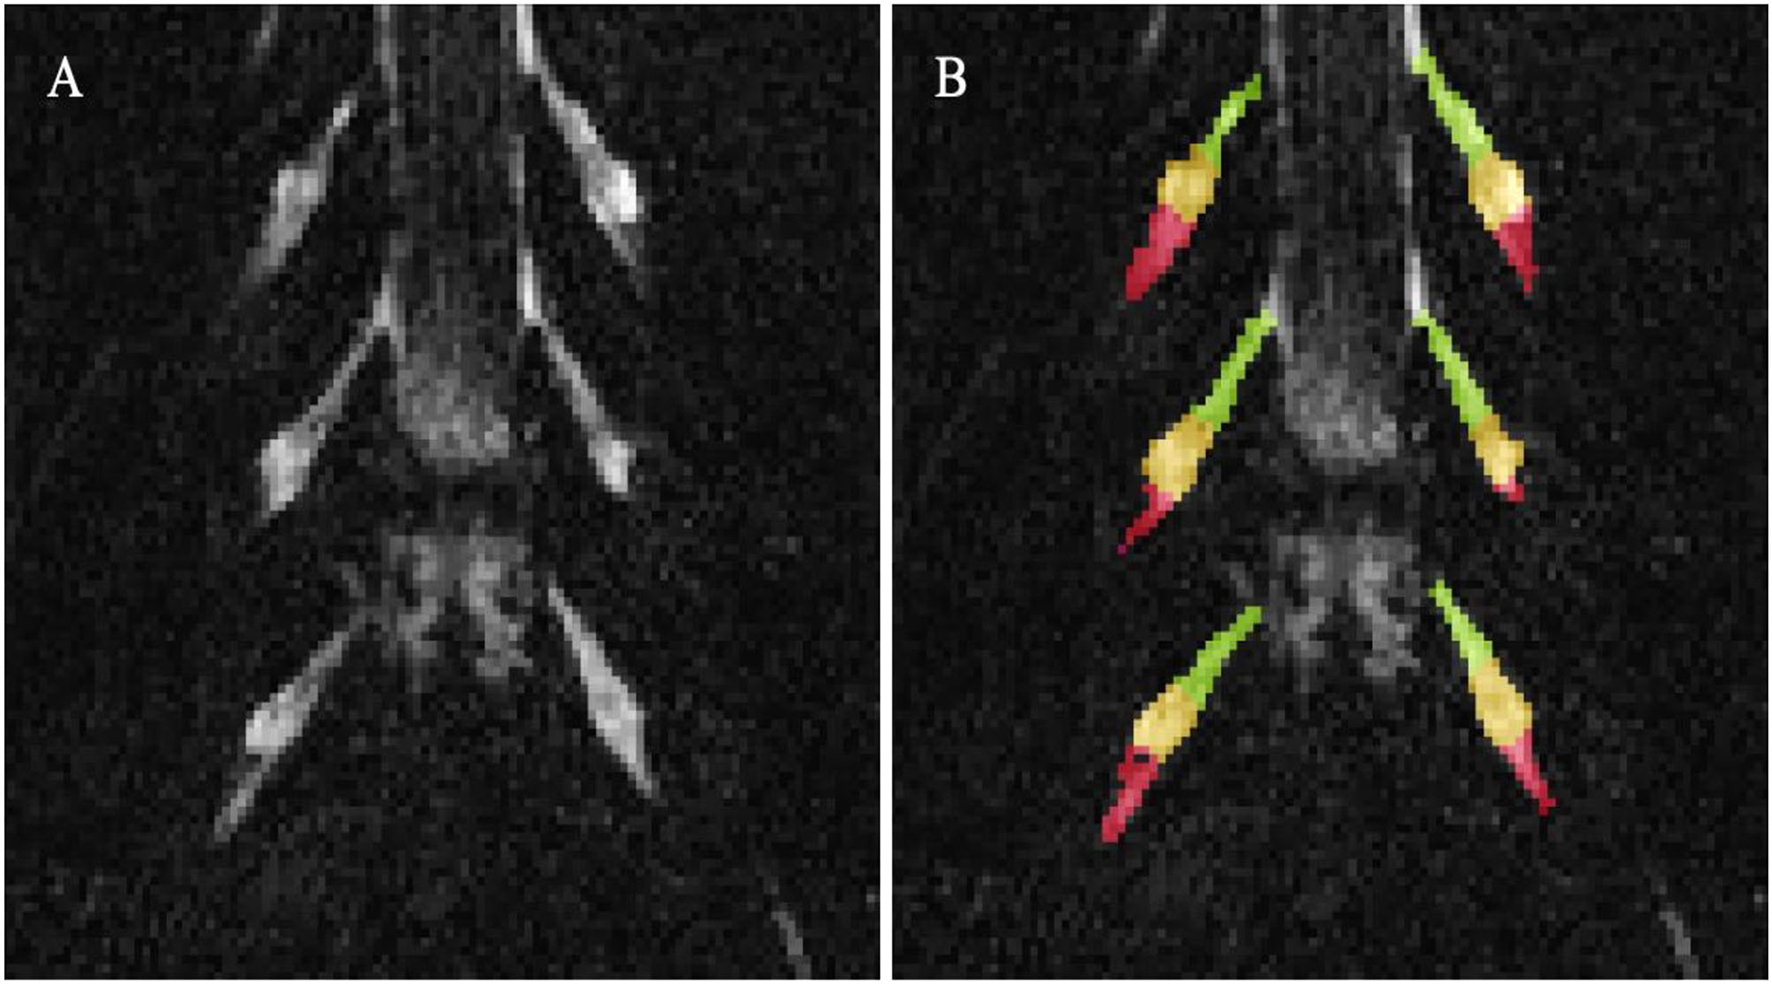

Image segmentation was performed manually in FSLview (http://www.fmrib.ox.ac.uk/fsl/). For the lumbar plexus, each lumbar segment (L2-L5) was manually segmented on the 3D SHINKEI images, with separate binary masks created for the preganglionic, ganglionic and post ganglionic regions (Figure 1). The sciatic nerve was segmented manually on fat-suppressed T2-weighted images (Figure 2), with separate binary masks created for each slice. All MTR volumes were co-registered to their respective 3D SHINKEI (plexus) or 2D fat-suppressed T2-weighted volumes (sciatic nerve) using affine registration with NiftyReg (23), to obtain global and region-specific MTR values.

Figure 1

(A) Example image obtained using the 3D SHINKEI at the level of the lumbar plexus (L2-L4 segments shown); (B) Manual segmentation of the lumbar segments with separate binary masks created for the preganglionic (green), ganglionic (yellow), and postganglionic (red) regions.